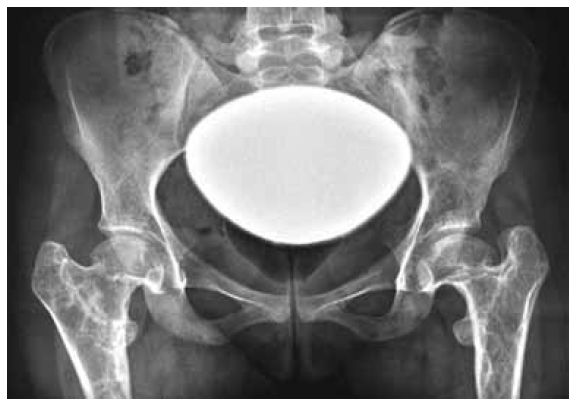

Radiographic examination: AP radiograph of the pelvis showed bilateral coxa vara associated with expansile lytic lesion with ground glass matrix was seen bilaterally involving the proximal femora shaft and the greater trochanter with significant deformity seen in the proximal femoral region. Ring-like calcification suggesting cartilage was well appreciated. Note the hypoplastic capital femoral epiphyses and the defective modelling of the neck of the femur. There is a shortage of the femoral neck with pathologic ATD (articular trochanteric distance) of (minus) 7 mm left and (minus) 5 mm right (Fig. 1).

Fig. 1. AP radiograph of the pelvis showed bilateral coxa vara associated with expansile lytic lesion with ground glass matrix was seen bilaterally involving the proximal femora shaft and the greater trochanter with significant deformity seen in the proximal femoral region. Ring-like calcification suggesting cartilage was well appreciated. Note the hypoplastic capital femoral epiphyses and the defective modelling of the neck of the femur. There is a shortage of the femoral neck with pathologic ATD (articular trochanteric distance) of (minus) 7 mm left and (minus) 5 mm right